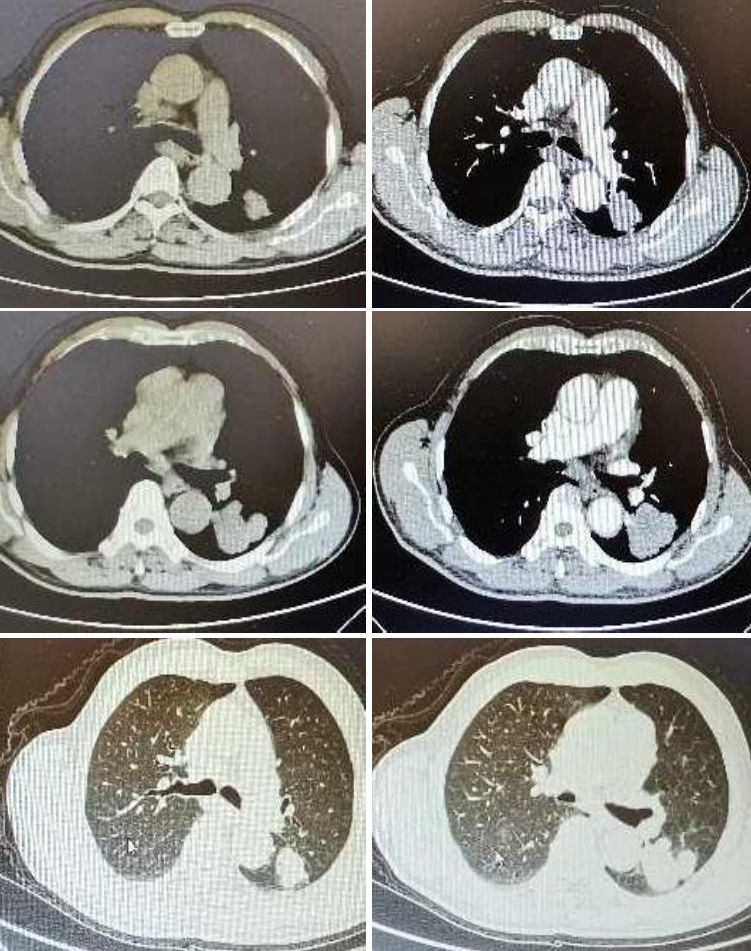

男性,75 岁,左上肢无力1 周。

诊断:肺癌脑转移。患者老年男性,影像特征是小病灶大水肿,考虑转移瘤。补充患者胸部CT如下: